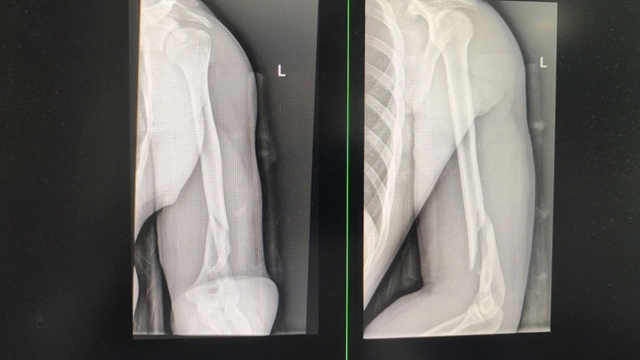

林浩被立即送往当地医院就诊,完善X光检查提示:左肱骨骨折。医生立即予以对症止痛、石膏外固定+三角巾悬吊治疗。医生看着林浩的X光片,惋惜地说到,“哎,骨头断了,需要开刀上钢板才行。”

科室王念武主治医师接诊后,详细检查了林浩的手臂,查看了X光片,发现林浩的骨折为闭合性骨折,虽然肿胀严重,但没有神经血管损伤,手法复位后能达到复位标准,则不影响后期功能恢复,且患者才23岁,新陈代谢能力强,恢复快,可以采用中医正骨保守治疗。

医生立即进行手法复位,在助手的默契配合下,只见王念武气定神闲,手法娴熟地施展起中医正骨绝技 ——“一牵,二折,三顶”。他的双手精准发力,一牵之下,骨折处间隙被巧妙拉开,为复位创造条件;紧接着顺势一折,瞬间纠正骨折错位;最后轻轻一顶,骨折断端严丝合缝,整个过程一气呵成,如行云流水般顺畅自然,眨眼间,骨折部位便完美复位。